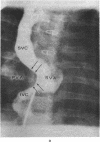

Scanning suprasternal echocardiography was performed in 280 patients with a variety of cardiac anomalies. By using the special suprasternal transducer on the suprasternal notch, the aortic arch, right pulmonary artery, and left atrium were recorded superoinferiorly. From this reference position various scanning techniques were made to record the main pulmonary artery, pulmonary valve, ascending aorta, aortic valve, and distal aortic arch, wherever possible. These scans made it possible to assess (a) the integrity and size of right pulmonary artery and main pulmonary artery in pulmonary atresia, stenosis of origin of right pulmonary artery, pulmonary artery banding, kinked Waterston anastomosis, and aneurysm of pulmonary artery; (b) relative positions of aortic valve and pulmonary valve in malposition complexes; (c) the position and size of the aortic arch in tetralogy of Fallot and aortic coarctation. Measurements of the left atrium made by suprasternal echocardiography were consistently larger than those made by praecordial echocardiography. Changes in relative sizes of aortic arch, right pulmonary artery, main pulmonary artery, and left atrium were also documented in the various cardiac anomalies. The atrial baffle after Mustard repair for d-transposition of the great arteries and the atrial membrane in cor triatriatum were also demonstrated. The introduction of scanning techniques has thus widened the scope of suprasternal echocardiography.